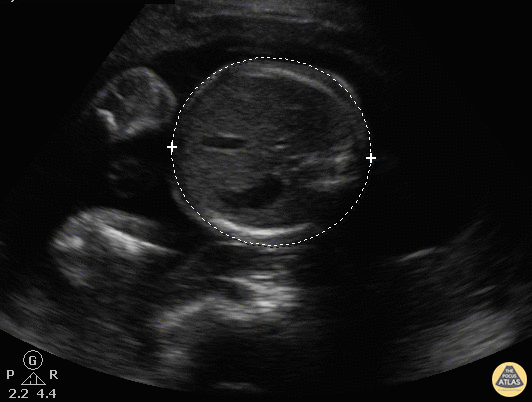

OB Dating Atlas - Week 25 - Abdominal Circumference (AC)

A 19-year-old G0 with an unknown LMP presents for a missed period and light vaginal bleeding. UPT is positive and on abdominal ultrasound, abdominal circumference measures 21.4 cm confirming a 25w6d IUP. General Rules: Measure the in the transverse section around the skin line making sure to be in the same plane as the stomach, umbilical vein, and portal sinus It is important to take multiple measurements here, as measurements can be altered due to fetal breathing motion. Accuracy [3]: ± 7-17 days